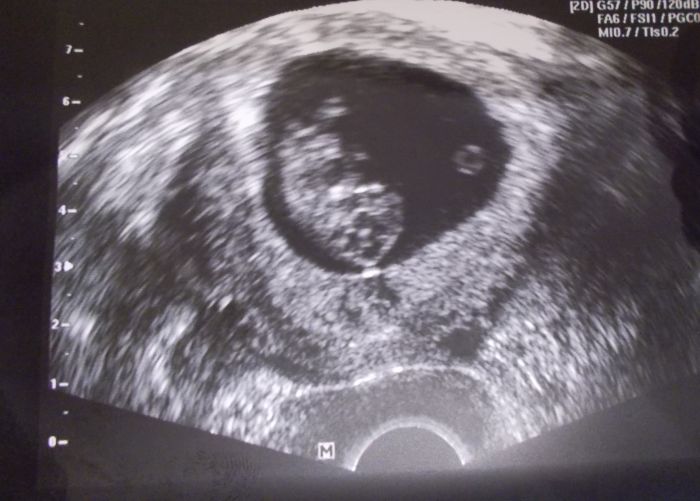

Je Marti krasna prdelinka ;-)

Marti krasna fazolka. Gratuluji.